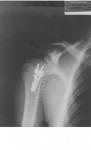

The Philips BuckyDiagnost, a technologically-advanced X-ray system, provides onsite X-ray capabilities inside the Yankees clubhouse. The system comes with a tool that creates crisp digital diagnostic images, which are available to team doctors almost instantaneously. The system also has multiple features that reduce unnecessary X-ray exposure while maintaining image quality.

“Determining the extent of an injury quickly and effectively is critical to getting the player the best course of action and onto the road to recovery,” said Christopher Ahmad, M.D., team physician for the New York Yankees. “Having a Philips X-ray system onsite will speed diagnosis and help us determine an appropriate course of treatment for players. Digital images are available within seconds and can be transferred electronically if care is required outside of the clubhouse.”